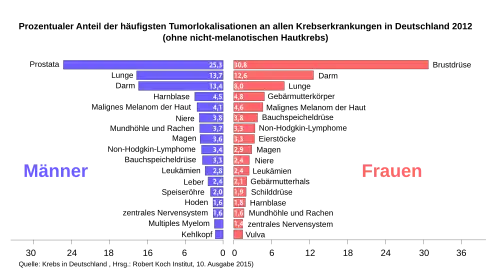

Das Pankreaskarzinom, der mit Abstand häufigste Pankreastumor, verursacht in Deutschland etwa 14.000 Neuerkrankungen jährlich – die Neuerkrankungsrate liegt bei rund 18 pro 100.000 Einwohner und Jahr.[13] In der deutschen Krebsstatistik steht es bei Männern an der zehnten, bei Frauen an der neunten Stelle (Stand: 2006). Bei den Krebstodesfällen belegt es den vierten Platz.[14] Die Erkrankten sind meist älter als 60 Jahre. Männer sind häufiger betroffen als Frauen (1,6:1). In der Schweiz erkrankten von 2010 bis 2014 durchschnittlich 1292 Menschen pro Jahr (51,5 % Frauen; 48,5 % Männer) und starben 1177 Menschen pro Jahr.[15] Seit einigen Jahren werden in Expertengremien Signale für eine zunehmende Inzidenz diskutiert, es liegen jedoch häufig nur fragmentierte epidemiologische Daten und Auswertungen vor. Unter Zugrundelegung der Datenbank “Surveillance, Epidemiology, and End Results” (SEER), die 37 % der US-Bevölkerung erfasst, wurde nun die Veränderung der Inzidenz seit Beginn des Jahrtausends als durchschnittliche jährliche prozentuale Veränderung beschrieben. Hierbei wurden zwischen 2000 und 2018 insgesamt 283.817 Pankreaskarzinome erfasst. Es zeigt sich sowohl bei Frauen als auch bei Männern ein Anstieg der Inzidenz. Auffällig war, dass besonders bei jüngeren Frauen (<55 Jahre) die Erkrankungshäufigkeit anstieg. Trotz erwartungsgemäß sehr niedriger Gesamtinzidenz ist diese Zunahme bei 15–34-Jährigen besonders ausgeprägt.[16]